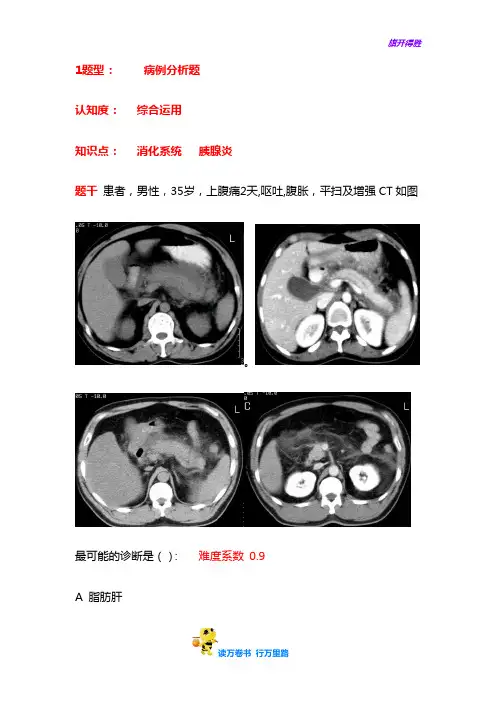

1题型:病例分析题认知度:综合运用知识点:消化系统胰腺炎题干患者,男性,35岁,上腹痛2天,呕吐,腹胀,平扫及增强CT如图。

最可能的诊断是():难度系数0.9A 脂肪肝1B 急性胰腺炎C胰腺癌D腹腔积液答案:B1、急性胰腺炎的可能病因:()难度系数0.9A胆石症与胆道疾病B 大量饮酒和暴饮暴食C 感染D 手术与创伤答案:ABCD解析:ABCD都是急性胰腺炎病因。